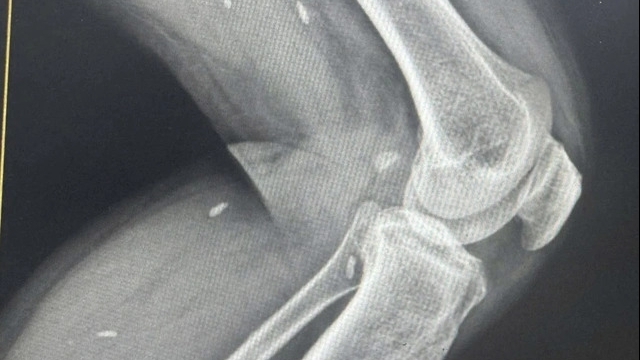

Ngày 23/10, bác sĩ Thân Trọng Tùy, Khoa Phẫu thuật Tạo hình thẩm mỹ và Phục hồi chức năng, Bệnh viện Da liễu Trung ương, cho biết các bác sĩ tại đây vừa tiếp nhận trường hợp bé gái 13 tuổi (ngụ Yên Bái) nhập viện trong tình trạng bị biến chứng nặng nề sau tiêm filler (chất làm đầy) để nâng mũi. Đáng nói là do kỹ thuật tiêm không đúng đã khiến mắt phải cháu bé mất hoàn toàn thị lực, vùng da mặt hoại tử nghiêm trọng.

Trước đó bệnh nhân đã khám mắt tại bệnh viện Mắt TW, các bác sĩ xác định mắt phải của bệnh nhân đã mất thị lực hoàn toàn và không thể điều trị được.

Sau khi khám xét nghiệm và hội chẩn các bác sĩ chuyên khoa da liễu đã tiêm thuốc giải chất filler do cơ sở thẩm mỹ đã tiêm vào mũi bé gái, đồng thời cố gắng cứu vùng da bị hoại tử, bảo tồn vùng da lành xung quanh cho bệnh nhân.

Theo bác sĩ Tùy, trường hợp của bé gái là do tiêm vào mạch máu gây tổn thương tắc mạch:

"Do tắc mạch nên gây hoại tử của mắt bên phải và các vùng da xung quanh được cấp máu bởi các nhánh của mạch bị tắc"